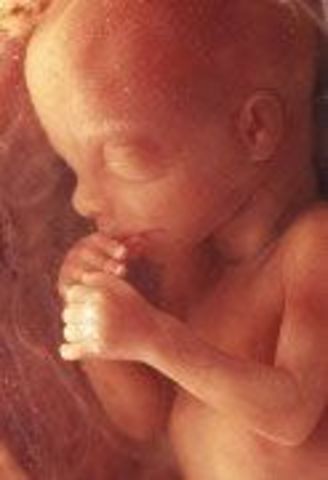

• Week 15: Bones and Muscle growth

Week 15: Bones and Muscle growth

The fetus, which can now be called a baby is 10cm in length and weighs about 2.5 oz. The skin is thin, the body is longer than the head and the arms and legs have grown. The baby's muscles and bones are continuously growing and adult taste buds have developed.

Facts: -The fetal crown to rump length by this week of pregnancy is 4 to 4.5 inches

-The baby's thin skin is covered with ultra fine, downy hair